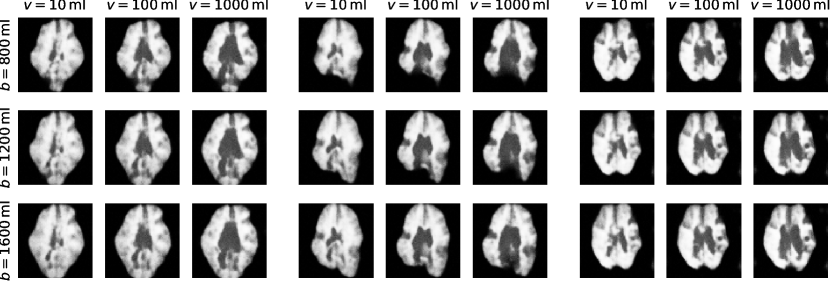

The original three-dimensional (3D) T1-weighted brain MRI scans have been pre-processed by the data providers of the UK Biobank Imaging study using the FSL neuroimaging toolkit [59]. The pre-processing involves skull removal, bias field correction, and automatic segmentation of brain structures. In addition, we have rigidly registered all scans to the standard MNI atlas space using an in-house image registration tool, which enabled us to extract anatomically corresponding mid-axial 2D slices that were used for the experiments presented in this paper. The 2D slices were normalised in intensity by mapping the minimum and maximum values inside the brain mask to the range . Background pixels outside the brain were set to zero. Age and biological sex for each subject were retrieved from the UK Biobank database along with the pre-computed brain and ventricle volumes. These volumes are derived from the 3D segmentation maps obtained with FSL, and although these are image-derived measurements, they may serve as reasonable proxies of the true measurements within our (simplified yet plausible) causal model of the physical manifestation of the brain anatomy.

B.2 Experimental Setup

The setup for the brain imaging experiment closely follows the MNIST example as described in Section A.2. We randomly split the available brain images into train, validation and test sets with the respective ratios , and . During training, we randomly crop the brain slices from their original size of to and use center crops during validation and testing. The cropped images are downsampled by a factor of to a size of .

We use the same low-level mechanism for the image as with MNIST images but change the encoder and decoder functions to a deeper architecture with 5 scales consisting of 3 blocks of each as well as a linear layer that converts to and from the latent space with dimensions. We directly learn the binary probability of the sex and use the following invertible transforms to model the age , brain volume , and ventricle volume as

B.3.1 Association